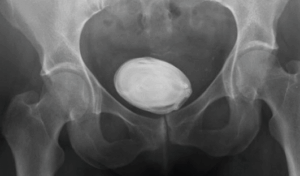

4. Bladder Stones

When we mentioned that Bladder infections occurred because of bacteria staying trapped inside the bladder…  well, now imagine that when the urine is unable to be emptied, that concentrated urine will crystallize, form tiny minerals and eventually form into stones.  Now, small bladder stones may pass without treatment, but sometimes bigger stones (like the one shown in the X-ray below) need treatment as these may lead to infections and other complications that may include:

a.     Lower abdominal painb.     Pain during urination

c.      Frequent urination

d.     Difficulty urinating or interrupted urine flow

e.     Blood in the urine